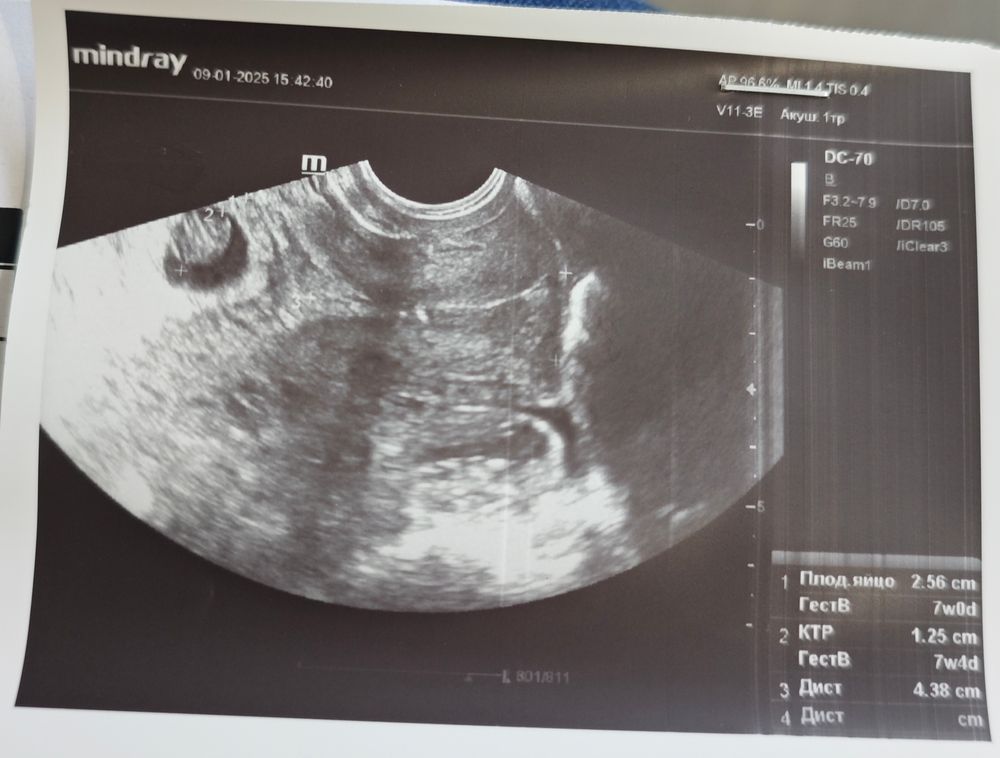

Сходила 9 января на первое УЗИ. По моим подсчётам в 7 недель ровно, а на УЗИ на два дня меньше указали срок по М почему-то. В прошлую Б на день меньше было. В целом все хорошо. Бусинка даже больше чуть по сроку, но единственное, что меня смущает - это то, что ПЯ на 4 дня меньше эмбриона по размерам по сроку получается. Вроде это не критично, но переживаю, что малышу может быть мало места.